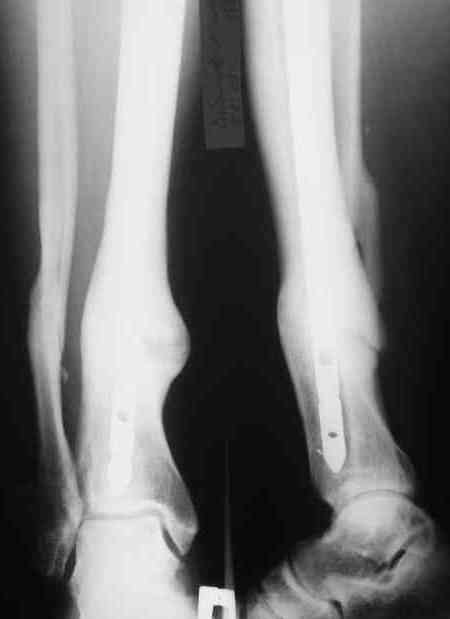

Год назад на форуме обсуждался случай не совсем удачного

интрамедуллярного синтеза большеберцовой кости.Номер в архиве 3392 от

27.10.07. Были предложены различные алгоритмы оперативного лечения.

Больной от повторной операции отказался. сейчас полная функция, полная

консолидация, занимается спортом.